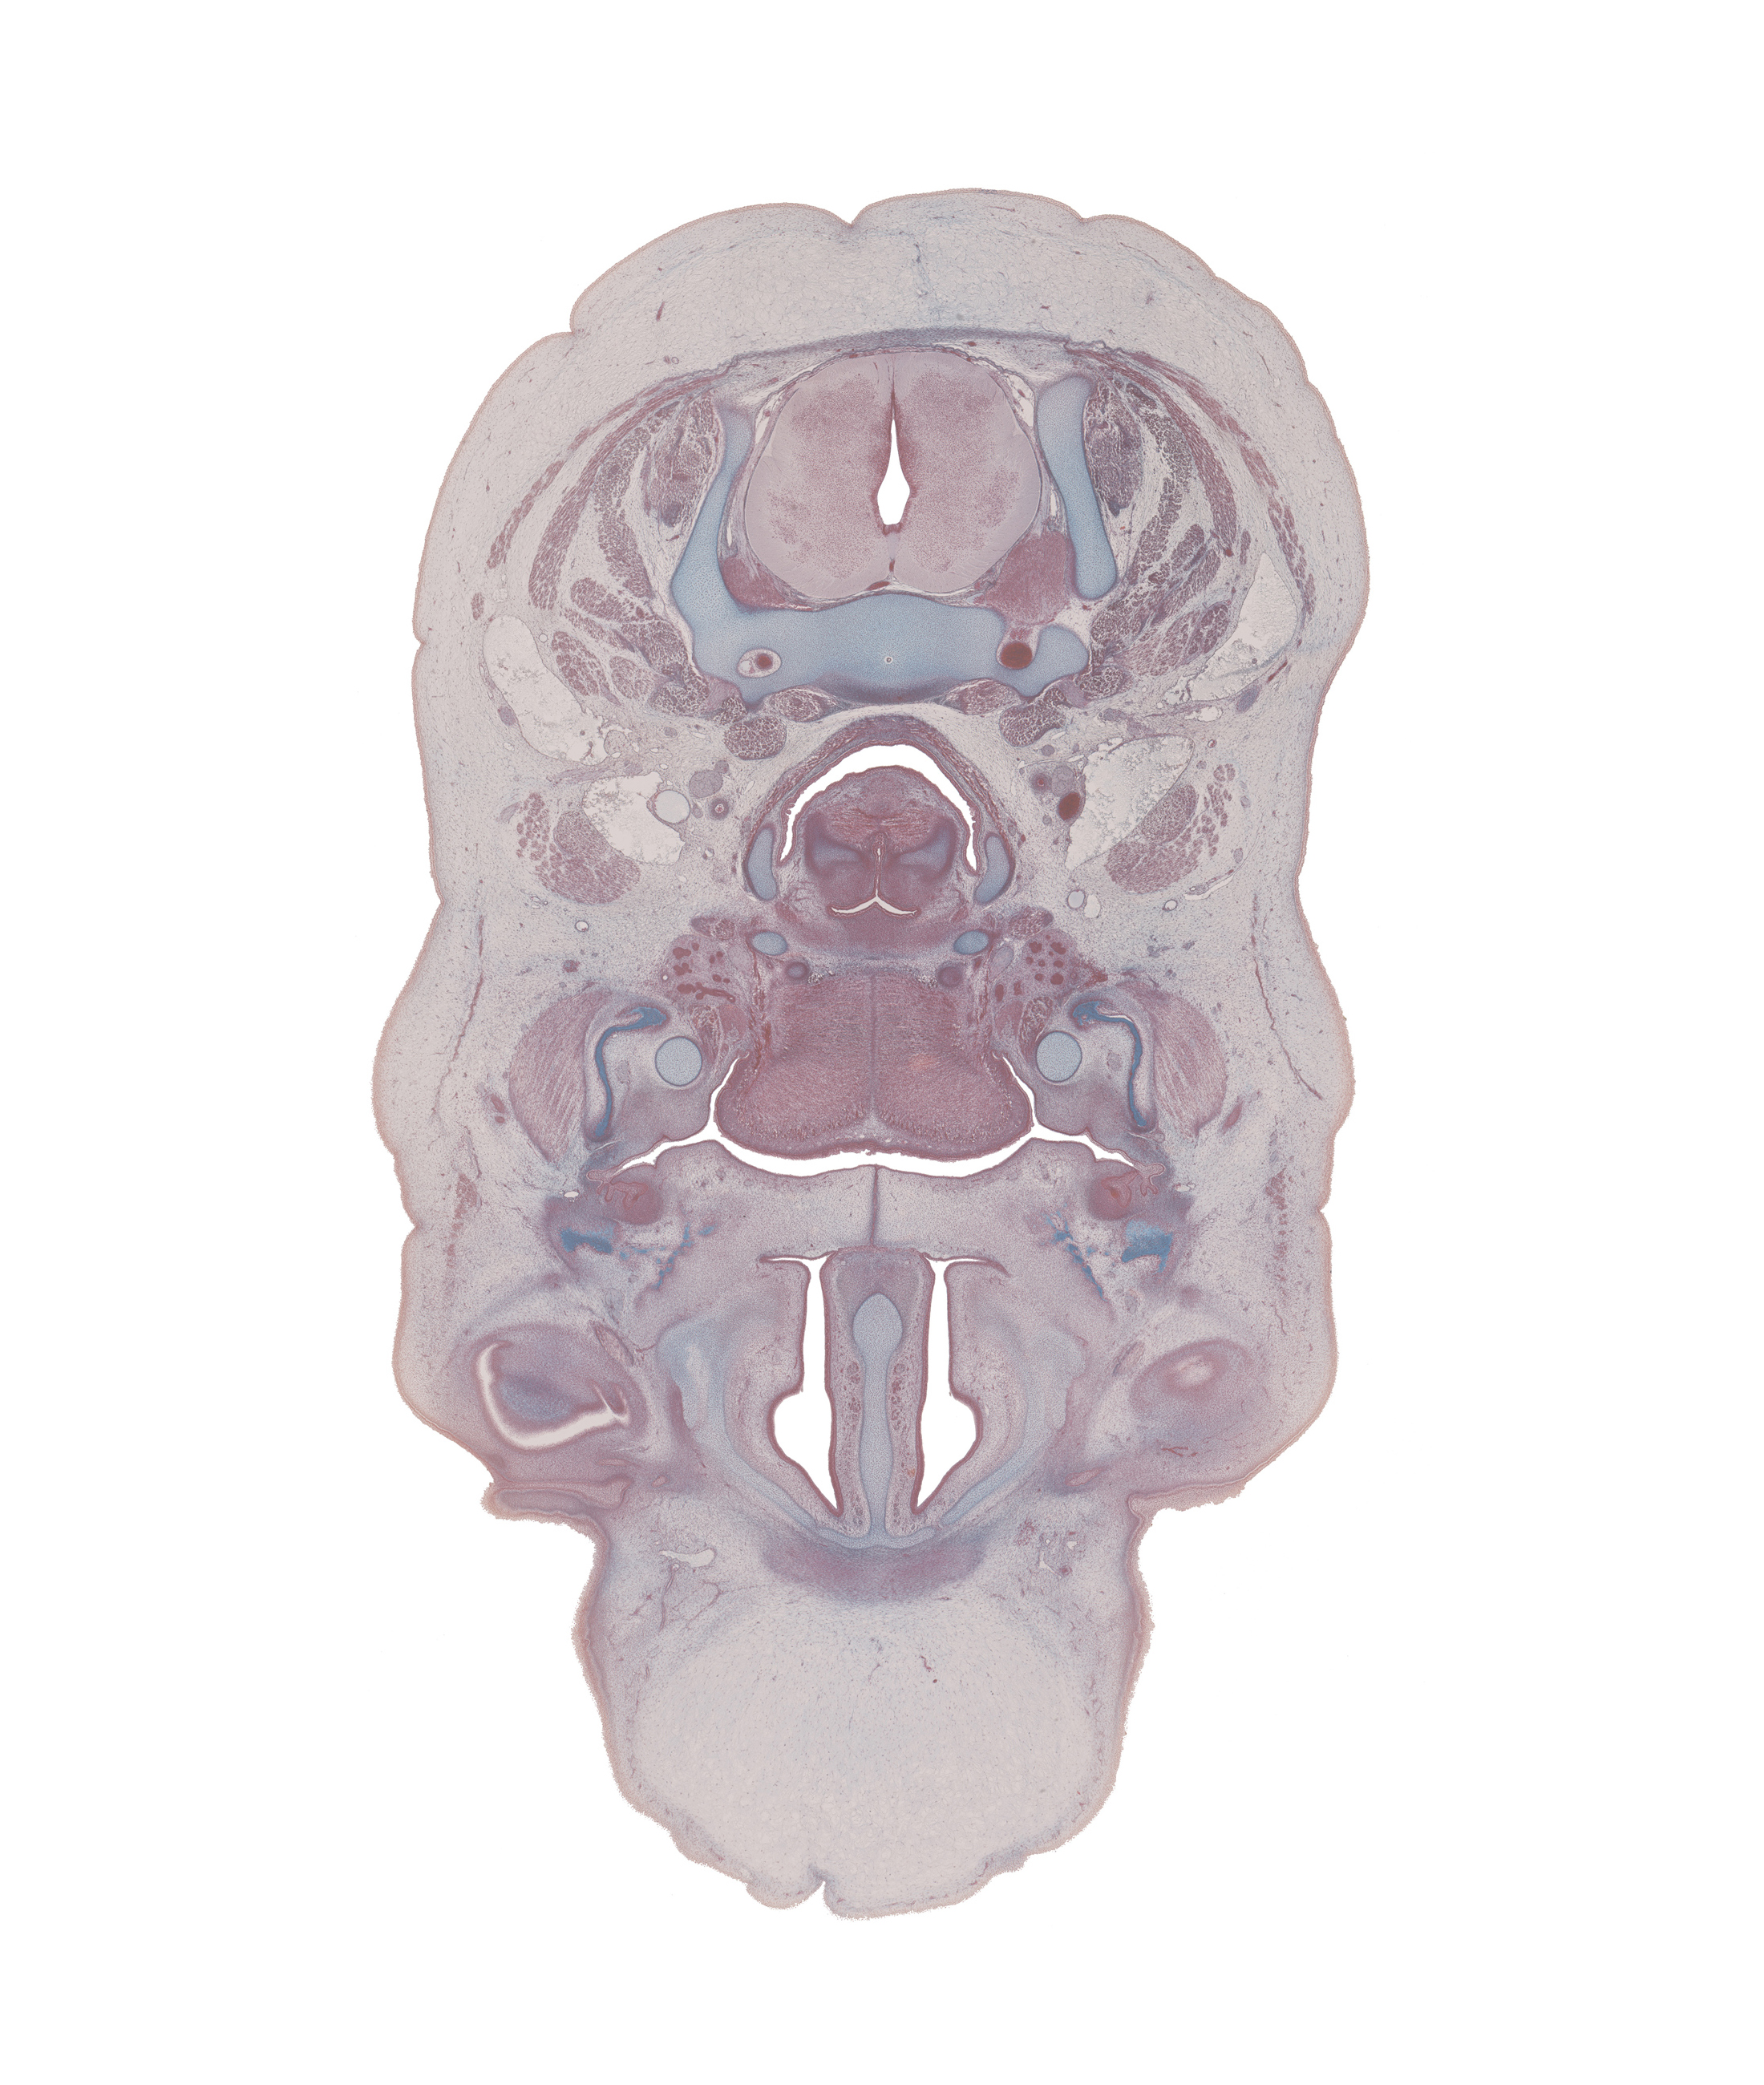

0 μm

Carnegie Embryo #9226 | Location: 77-01-01

Keywords: C-5 spinal ganglion, body of tongue, common carotid artery, conjunctival sac, edge of eyeball, fusion region of palatine shelves, greater horn of hyoid (pharyngeal arch 3 cartilage), internal jugular vein, interorbital ligament, jugular lymph sac, lesser horn of hyoid (pharyngeal arch 2 cartilage), linguogingival sulcus, lymph sac, masseter muscle, middle pharyngeal constrictor muscle, parotid duct, platysma muscle, retropharyngeal space, sternocleidomastoid muscle, sympathetic trunk, vagus nerve (CN X)

Source: The Virtual Human Embryo.